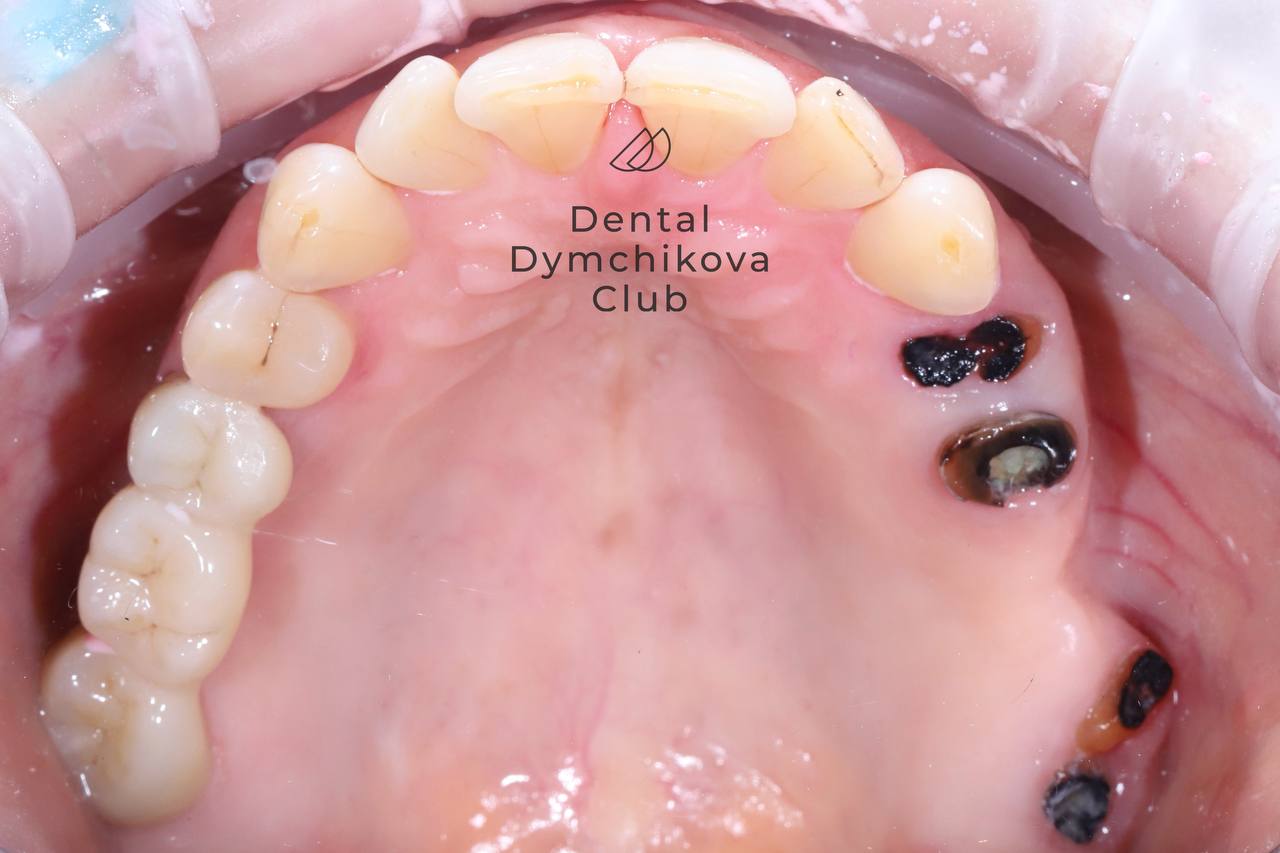

Ортодонтическое лечение, синус-лифтинг, имплантация, протезирование, лечение кариеса

Пациент, 33 года.

Жалобы: на неровные зубы, желание поменять мосты на задних зубах.

Исходные данные: скученность зубов, наличие кариесов, недостаток кости по высоте для установки имплантатов.

Лечение:

1) санация полости рта (лечение кариеса),

2) ортодонтическое лечение (брекеты, минивинты),

3) синус-лифтинг и имплантация в области отсутствующих зубов на этапе ортодонтического лечения,

4) протезирование зубов и имплантатов коронками.

Срок лечения: 2,4 года.

Доктора: Ефимова Дарья Юрьевна, Дымчикова Анна Вавиловна, Лебедева Адиса Тумэновна.